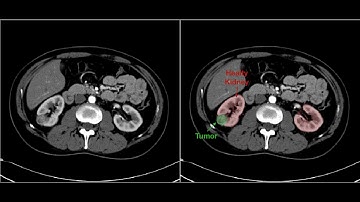

Cell Detection with AI| +91-9872993883 for query| Using Image Segmentation in MATLAB |